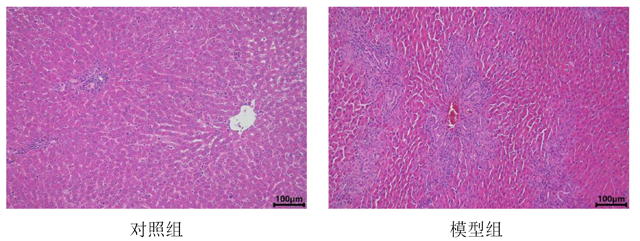

肝组织HE染色

在预定的时间点(如术后数天或数周),处死动物并取出肝脏组织进行病理学检查。观察肝脏的形态学变化,如肝小叶结构失常、纤维组织增生等。可采用血清学检测等方法评估肝功能的变化,如胆红素、转氨酶等指标。同时,可观察动物的黄疸情况,如皮肤、巩膜黄染等。详细如下表

术后3–7天 血清TBIL、ALT峰值,胆管直径扩张 肝细胞气球样变,小胆管增生